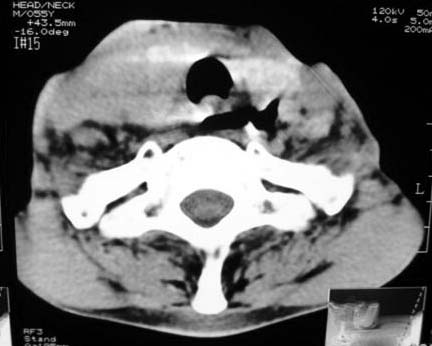

以下是引用dyqct在2007-4-20 16:19:00的发言:[br]考虑:1、左侧梨状窝区破裂伴左颈深、浅部气肿。[br] 2、右侧甲状腺区血肿(请追问病史是否伤及右颈部)。[br] 3、建议病情稳定后增强扫描除外右侧甲状腺腺瘤。